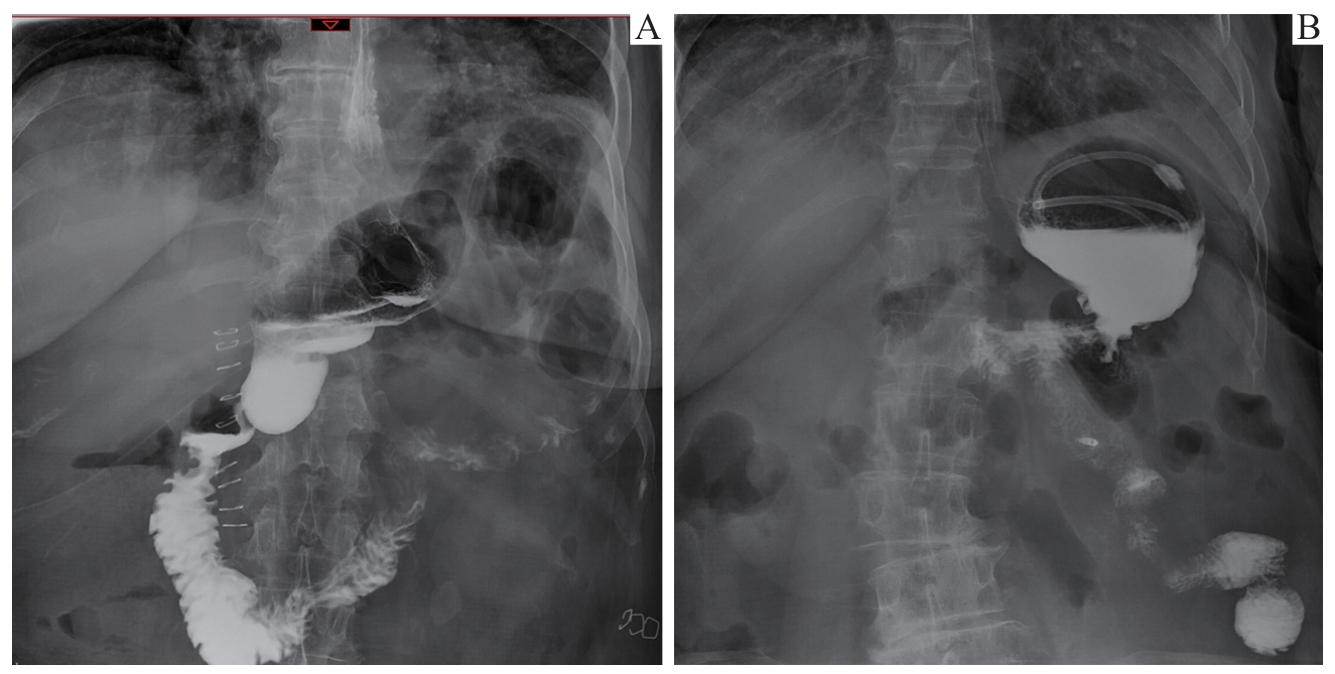

目的·比较分析机器人与腹腔镜辅助近端胃切除联合双肌瓣吻合术在治疗早期胃上部癌中的安全性及近期效果。方法·采用回顾性队列研究方法,分析2023年9月至2024年3月于上海交通大学医学院附属仁济医院胃肠外科行近端胃切除联合双肌瓣吻合进行消化道重建的31例早期胃癌患者临床病理资料。根据手术方式不同,将患者分为机器人辅助手术组(机器人组,20例)和腹腔镜辅助手术组(腹腔镜组,11例)。比较2组患者的一般临床资料、术中情况及术后恢复情况。术后6个月随访时,行上消化道造影和食管胃镜检查,判断是否有吻合口狭窄及反流性食管炎;同时,使用欧洲癌症研究与治疗组织(European Organization for Research and Treatment of Cancer,EORTC)的胃癌特异模块量表(Quality of Life Questionnaire-Stomach 22,QLQ-STO22)评估患者的生活质量。结果·2组患者的一般资料,包括性别、年龄、术前合并症、美国麻醉医师协会(American Society of Anesthesiologists,ASA)分级、Siewert分型以及肿瘤的病理分期,差异均无统计学意义(均P>0.05)。2组患者均顺利完成手术,无中转开腹。机器人组的胃食管吻合时间较腹腔镜组显著缩短[(31.09±8.23)min vs (43.73±8.83)min,P<0.001],而术中及术后各项指标,包括手术时间、术中失血量、淋巴结清扫数、术后胃管留置时间、术后流质饮食开始时间、术后住院天数以及术后并发症发生率在2组之间差异均无统计学意义(均P>0.05)。术后6个月随访共有30例患者完成(其中机器人组失访1例)。上消化道造影及食管胃镜检查结果显示,仅腹腔镜组1例患者出现吻合口狭窄,机器人组出现A级和B级反流性食管炎各1例,腹腔镜组出现B级反流性食管炎1例。2组反流性食管炎和吻合口狭窄发生率差异均无统计学意义(均P>0.05)。EORTC QLQ-STO22评分结果显示,机器人组在吞咽困难、胃食管反流、饮食受限3个维度的评分,以及量表总分均显著低于腹腔镜组(均P<0.05)。结论·机器人辅助近端胃切除联合双肌瓣吻合手术安全可行,术中吻合时间更短,且在术后功能恢复和患者生活质量提升方面具有潜在优势。

Objective ·To compare the safety and short-term outcomes of robot-assisted versus laparoscopic-assisted proximal gastrectomy combined with double-flap esophagogastrostomy in the treatment of early upper gastric cancer. Methods ·A retrospective cohort study was conducted to analyze the clinical and pathological data of 31 early gastric cancer patients who underwent proximal gastrectomy combined with double-flap esophagogastrostomy for gastrointestinal reconstruction at the Department of Gastrointestinal Surgery, Renji Hospital, Shanghai Jiao Tong University School of Medicine, from September 2023 to March 2024. Based on the surgical approach, patients were divided into the robot-assisted surgery group (robotic group, 20 cases) and the laparoscope-assisted surgery group (laparoscopic group, 11 cases). General clinical data, intraoperative conditions, and postoperative recovery between the two groups were compared. At the 6-month postoperative follow-up, upper gastrointestinal radiography and esophagogastroscopy were performed to assess anastomotic stricture and gastroesophageal reflux disease. Additionally, the gastric cancer-specific module of the European Organization for Research and Treatment of Cancer (EORTC), Quality of Life Questionnaire-Stomach 22 (QLQ-STO22), was used to evaluate the patients′ quality of life. Results ·The general data of the two groups, including gender, age, preoperative comorbidities, American Society of Anesthesiologists (ASA) classification, Siewert classification, and pathological staging of tumors, showed no statistically significant differences (all P>0.05). All patients successfully underwent the procedure without conversion to open surgery. The time for gastroesophageal anastomosis was significantly shorter in the robotic group compared to the laparoscopic group [(31.09±8.23) min vs (43.73±8.83) min, P<0.001], while there were no statistically significant differences in other intraoperative and postoperative parameters, including operative time, intraoperative blood loss, number of lymph nodes removed, duration of gastric tube placement, time to start a liquid diet, length of postoperative hospital stay, and incidence of postoperative complications (all P>0.05). At the 6-month postoperative follow-up, 30 patients completed the follow-up, with one patient lost to follow-up in the robotic group. Upper gastrointestinal radiography and esophagogastroscopy results showed that only one patient in the laparoscopic group developed an anastomotic stricture, while one patient in the robotic group developed grade A and one developed grade B gastroesophageal reflux disease (GERD). In addition, one patient in the laparoscopic group also developed grade B GERD. The incidences of GERD and anastomotic stricture showed no statistically significant differences between the two groups (both P>0.05). EORTC QLQ-STO22 results indicated that the robotic group had significantly lower scores in the dimensions of dysphagia, gastroesophageal reflux, and dietary restrictions, as well as in the total score, compared to the laparoscopic group (all P<0.05). Conclusion ·Robot-assisted proximal gastrectomy combined with double-flap esophagogastrostomy is safe and feasible. It shortens anastomosis time and offers potential advantages in postoperative functional recovery and quality of life improvement.